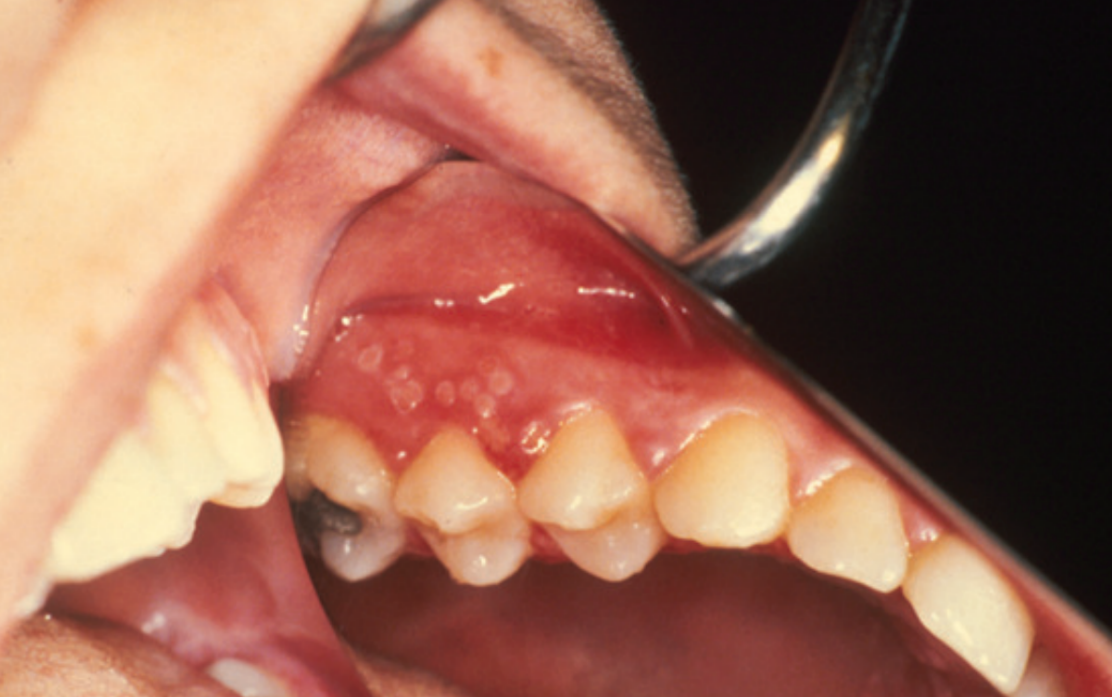

6.9 Mucoceles

A mucocele is a cyst-like swelling caused by saliva build-up within subcutaneous tissue following damage to salivary ducts.

A mucocele is the most common nodular swelling of the lower lip[Text Wrapping Break][Text Wrapping Break]

Signs and symptoms

These swellings are asymptomatic, soft, fluctuant, bluish grey (although long standing lesions may have a whitish appearance) and are usually less than one centimetre in diameter. Saliva builds up in connective tissue, which is surrounded in a fibrous capsule. The most common location is the lower lip.

Causes

Arises from trauma to one of the minor salivary glands in the lips or cheeks. Often caused by lower-lip biting or other minor injuries.

Age

Can occur at any age. Children and young adults are mostly affected.

Duration

Superficial lesions usually burst and heal within three to six weeks, they may reform as the tissue fills with saliva again. Persistent lesions require treatment for resolution.

Treatment

Superficial mucoceles usually burst and heal spontaneously. Persistent mucoceles are treated by surgical excision.

The development of a bluish swelling after trauma is suggestive of a mucocele; investigation by a dental practitioner is suggested to exclude other lesions.